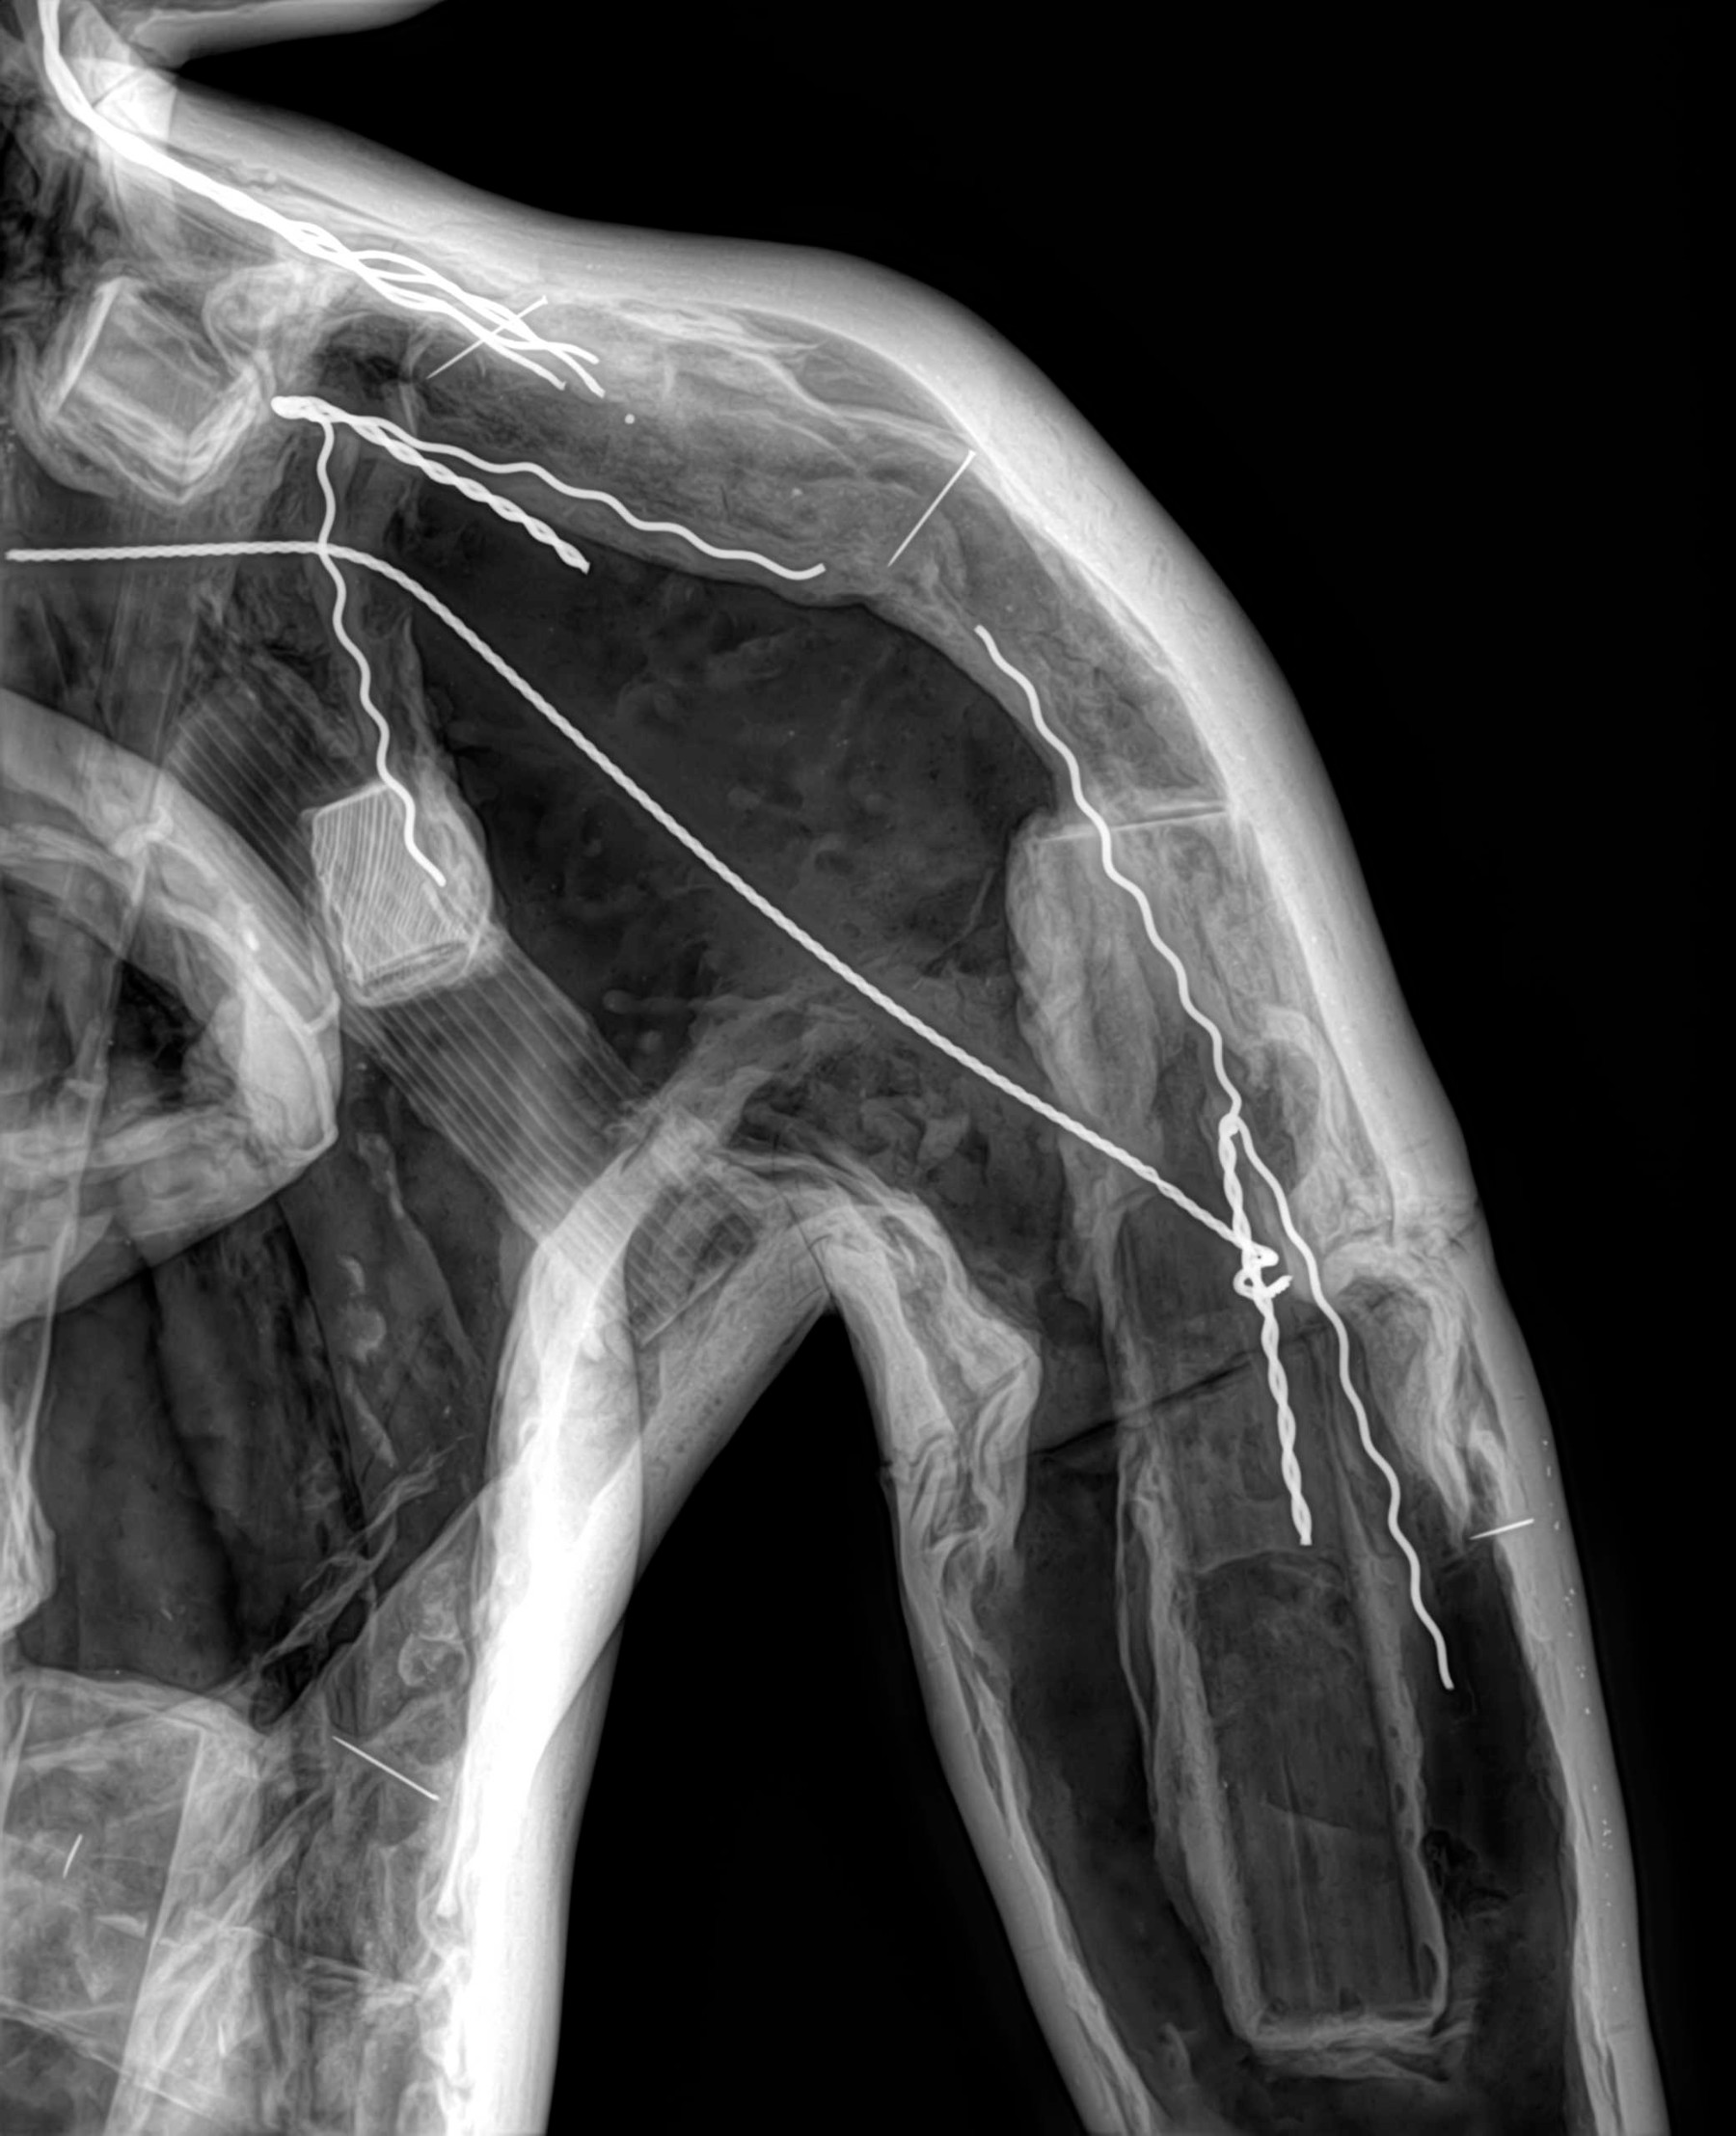

Radiología Digital como Herramienta Complementaria en el Dictamen de Bienes Muebles

Desde el descubrimiento de los rayos “X” y las placas radiográficas por Wilhelm Conrad Roentgen y su posterior difusión a través de la Asociación Físico médica de Wurzburg el 28 de diciembre de 1895, que fue la primera asociación que habló de los nuevos rayos que podían penetrar el cuerpo y fotografiar los huesos, ha habido muchos cambios tanto en la forma de obtener, procesar e incluso en la forma de visualizar, manejar y almacenar las placas radiográficas.